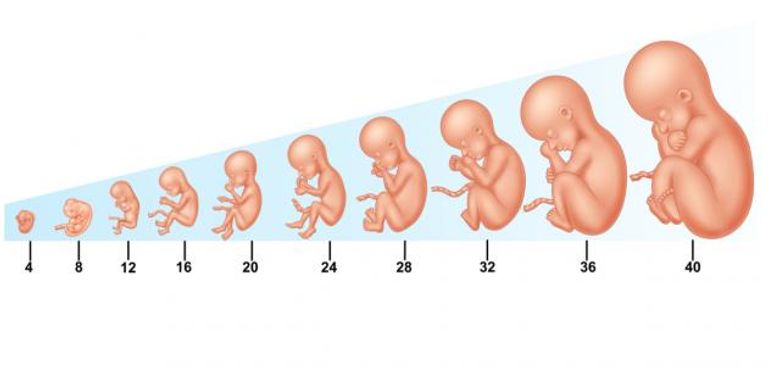

تصف الكثير من الآيات القرآنية مراحل تطور الجنين، وذلك قبل أن يكون هناك علم الأجنة الحديث بمئات السنين.

ووصفت مراحل تطور الجنين بدقة متناهية في سورة المؤمنون {وَلَقَدْ خَلَقْنَا الْإِنْسانَ مِنْ سُلالَةٍ مِنْ طِينٍ (12) ثُمَّ جَعَلْناهُ نُطْفَةً فِي قَرارٍ مَكِينٍ (13) ثُمَّ خَلَقْنَا النُّطْفَةَ عَلَقَةً فَخَلَقْنَا الْعَلَقَةَ مُضْغَةً فَخَلَقْنَا الْمُضْغَةَ عِظامًا فَكَسَوْنَا الْعِظامَ لَحْمًا ثُمَّ أَنْشَأْناهُ خَلْقًا آخَرَ فَتَبارَكَ اللَّهُ أَحْسَنُ الْخالِقِينَ (14 )}.

ويقول أسامة مرسي، استشاري أمراض النساء والتوليد بوزارة الصحة المصرية لـ”العين الإخبارية”، إن ما ذكره القرآن الكريم من تلك المراحل بدقة متناهية، كما جاء في سورة “المؤمنون”، احتاج الطب الحديث إلى تقنيات التصوير والأشعة الحديثة لإثباته، والتي ذهبت جميعها إلى براعة النص القرآني في وصف تفاصيل مراحل نمو الجنين.

ويوضح مرسي، هذا التلاقي بين النص القرآني وما أثبته العلم الحديث في العناصر الآتية، وفق ما جاء في سورة “المؤمنون”..

ووفق المنظور القرآني، يشير تكوين العلقة، كما جاء في بداية الآية 14 من سورة المؤمنون إلى التعلق الأولي للجنين النامي بجدار الرحم، وهو ما يطلق عليه علميا، كما يوضح مرسي، بـ”المرحلة الجنينية”، والتي تستمر من فترة الانغراس إلى حوالي 8 أسابيع من الحمل.

ويقول:” تتكاثر خلال تلك المرحلة، خلايا الجنين بسرعة، ويبدأ مخطط الجسم الأساسي بالتشكل، ويرتبط الجنين بجدار الرحم عن طريق هياكل مثل المشيمة والحبل السري”.

وتمثل كتلة اللحم (المضغة) التطور اللاحق من “المرحلة الجنينية”، إلى جنين، كما جاء في نفس الآية (14) من سورة المؤمنون.

ويقول مرسي: “في بداية تلك المرحلة (حوالي 9 أسابيع من الحمل)، أثبت العلم أن أجهزة وهياكل الأعضاء الرئيسية بالجسم تبدأ في التطور، ويأخذ الجنين مظهرا أكثر شبها بالإنسان”.

خامسا: تكوين العظام

وتذكر الآية “14” مرحلة تكوين العظام كمرحلة متميزة في تطور الإنسان، وهي العملية التي تحدث خلال مرحلة الجنين، وتسمى علميا بـ”التعظم”.

ويوضح مرسي أنه “في هذه المرحلة، تبدأ العظام في التشكل، ويتكون في البداية، الهيكل العظمي من الغضروف، الذي يتحول تدريجياً إلى نسيج عظمي”.

سادسا: كسوة العظام باللحم

بعد تكوين العظام، يذكر القرآن بداية مرحلة كسوتها باللحم، ويقول مرسي، إن “هذه المرحلة يشار لها علميا بأنها تلك التي تشهد نمو العضلات والأعضاء والأنسجة الرخوة الأخرى حول الهيكل العظمي، مما يوفر الشكل والدعم للجسم المتنامي”.

سابعا: مزيد من التطوير والتمايز

ويقر القرآن الكريم بأن التطور البشري يستمر إلى ما بعد تكوين العظام واللحم، مما يشير إلى مراحل أخرى من النمو والتمايز.

ويضيف مرسي أن “ذلك يتفق مع المنظور العلمي، الذي يقر بأنه طوال فترة الحمل، يمر الجنين بنمو وتطور مستمر، حيث تنضج أعضاؤه وأجهزته وتصبح وظيفية، وتستمر هذه العملية حتى الولادة وما بعدها”.